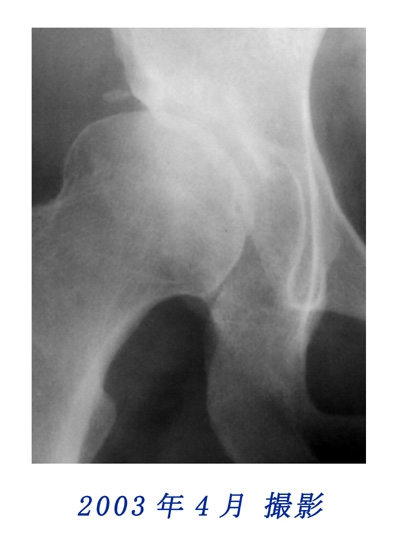

2000年6月と2003年4月のレントゲン写真を比較しても、変化は認めにくいのですが、2003年4月と2005年6月に撮影されたレントゲン写真の骨盤形状に顕著な変化を観察することができます。

右股関節の変化(部分拡大)

2003年と2005年に撮影されたレントゲン写真中、右の股関節にも顕著な変化を認められました。

右股関節の変化比較用

2003年と2005年のレントゲン写真の股関節部を拡大して重ねました。写真にカーソルを重ねると2003年と2005年の写真が入れ替わります。股関節の変化を観察してください。